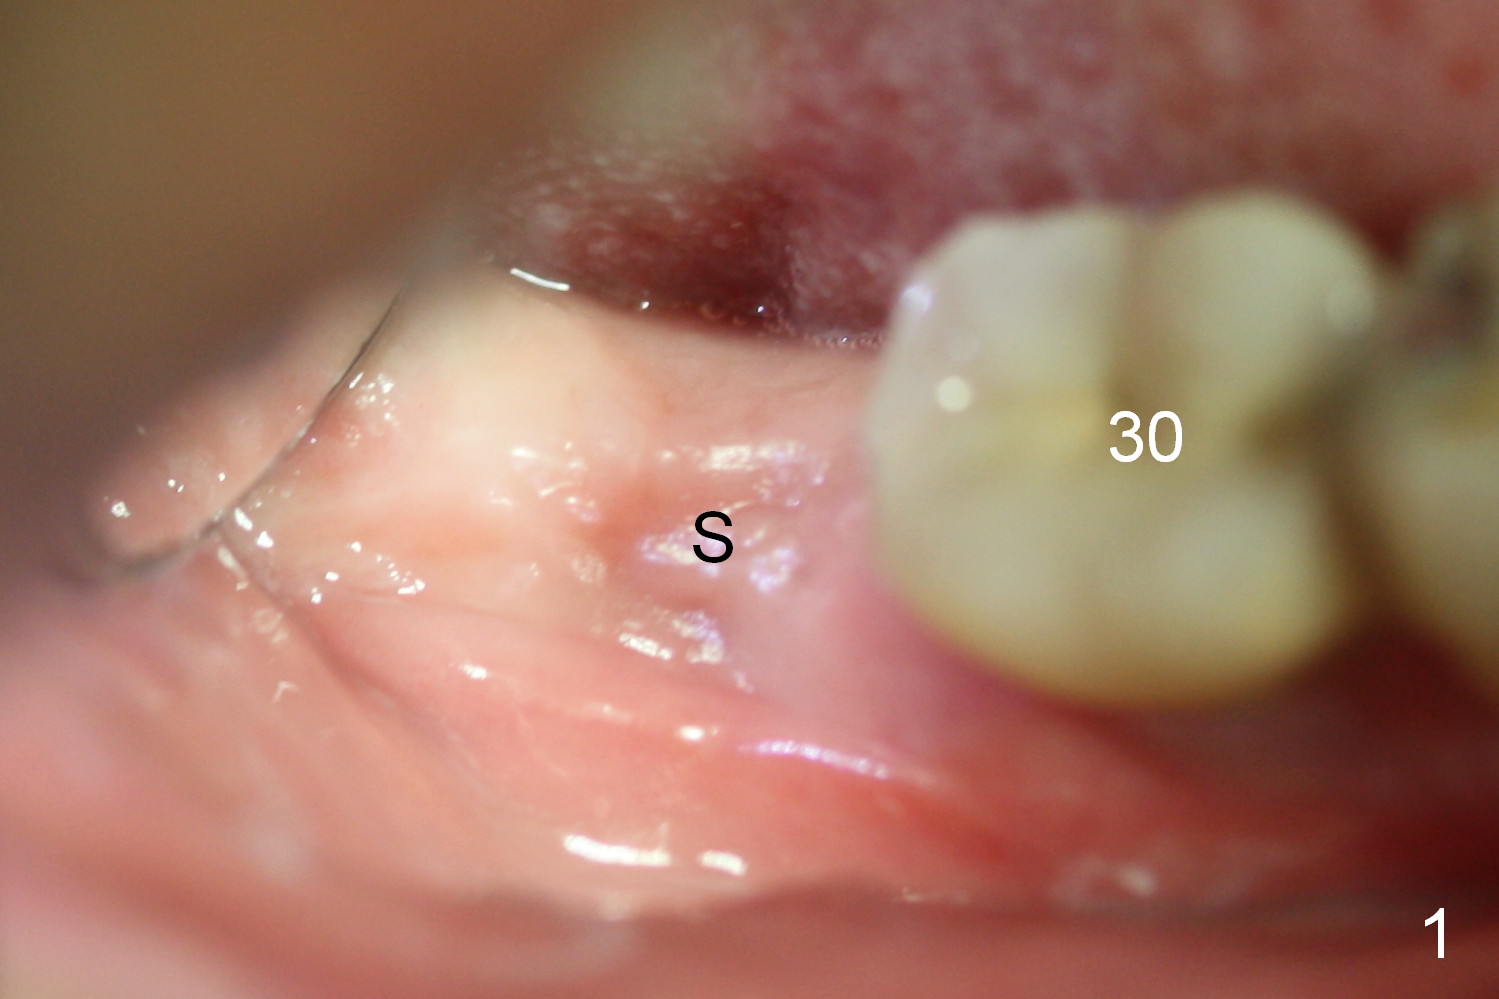

A 75-year-old man has apparent history of bruxism. The distal root of the tooth #31 had vertical fracture after root canal therapy. The tooth was extracted ~ 2 months ago while he returned to home country. It appears that there is buccal plate atrophy (Fig.1 S: socket).

Incision will be made to determine pattern of bone resorption and where to initiate osteotomy. Although the soft tissue of the socket (Fig.1 S) has healed, the bone must be still healing (soft, Fig.2 radiolucent socket). Use DIO starter drill, 2 mm pilot drill set at 12 mm (4 mm implant spacer) and short and marked parallel pins. Keep the last pin in place and take PA and photos. Change trajectory with Lindamann bur in the cassette if needed. Then start using bone expanders as large and deep as possible. The bone beyond the socket may be not as soft. Keep the largest expander in place and take photos. We want to confirm that not only is the buccal plate able to be expanded, but also the plate can be increased coronally to certain degree.